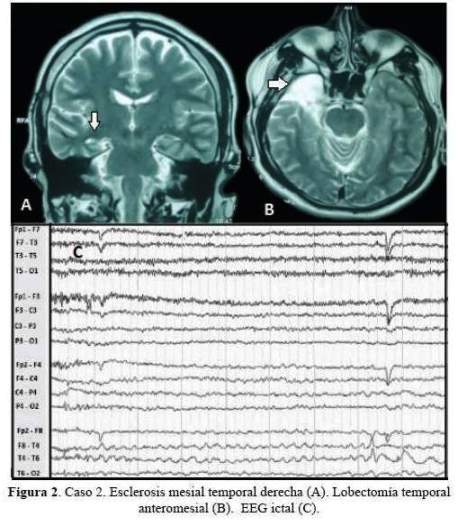

De los 5 casos, 3 cirugías correspondieron a pacientes con epilepsia temporal mesial derecha (2 por esclerosis mesial temporal y 1 por ganglioglioma mediobasal temporal anterior) y 2 correspondieron a patología dual (1 con EMT derecha más lesión gliótica cicatrizal de un angioma cavernoso temporal neocorical ipsilateral operado previamente y 1 con EMT izquierda más gliosis frontal ipsilateral). De los 3 pacientes con epilepsia temporal mesial derecha, 2 sólo requirieron de estudios paraclínicos en fase 1: EEG/VideoEEG y RM encéfalo estructural y 1 requirió además de PET interictal (fase 2), pues a pesar de que la semiología y actividad electrográfica ictal correspondían a una epilepsia del lóbulo temporal mesial derecho, la RM de encéfalo dejaba duda respecto a si además de tener EMT derecha,tenía también EMT izquierda. A estos tres pacientes se les realizó lobectomía temporal anteromesial (LTA) que incluyó amigdalohipocampectomía, siguiendo las técnicas quirúrgicas del Programa de Epilepsia del London Health Sciences Centre, University of Western Ontario, Canadá (20). Las 2 pacientes con patología dual fueron intervenidas con el apoyo de electrocorticografía (ECoG) aguda o intraoperatoria. En una de ellas se demostró que la lesión frontal izquierda ipsilateral era silente, no se resecó y se realizó solo LTA izquierda. En la otra paciente, la ECoG orientó a realizar una lesionectomía ampliada de la lesión neocortical temporal anterior; pero tuvimos que abstenernos de realizar una amgdalohipocampectomía a pesar de tratarse de una patología dual, pues su reserva cognitiva y la memoria, tanto verbal como visual estaban indemnes. Es importante señalar que en ésta paciente la semiología ictal inicial era neocortical (auras auditivas, seguidas solo después de segundos de miedo). En la primera paciente con patología dual además se realizó estimulación cortical directa para la evaluación intraoperatoria del lenguaje con la paciente despierta; se puede revisar en detalle el procedimiento en un reporte del caso publicado previamente (21). No se realizaron en esta serie resecciones extratemporales. Los resultados de anatomopatología evidenciaron como etiología definitiva: 3 EMT, 1 ganglioglioma y 1 gliosis reactiva; esta última corresponde a la paciente con patología dual con lesión gliótica cicatrizal neocortical temporal derecha, operada en años previos de angioma cavernoso en dicha zona. Las imágenes de RM de encéfalo y EEG de los casos 1, 2, 3 y 5 pueden ser revisadas en la figura 1,figura 2,figura 3 y figura 4 Las imágenes del caso 4 pueden ser revisadas en un reporte de caso publicado previamente (21).